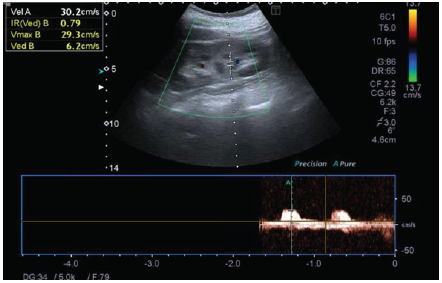

Immunoglobulins A, G, and M were normal; hematuria (150 erythrocytes/field) and proteinuria (750mg proteins in 24 hours) were found in urine, although proteinuria in the 24-hour urine for Bence Jones was negative. The albumin-to-creatinine ratio was 160 mg/g, and the protein-to-creatinine ratio was 760 mg/dL, and renal echo-Doppler showed an increase in resistance rates of intraparenchymal arteries (Figures 2 and 3).

Source: Document obtained during the course of the study.

Figure 3 Renal Doppler ultrasound of the left kidney.